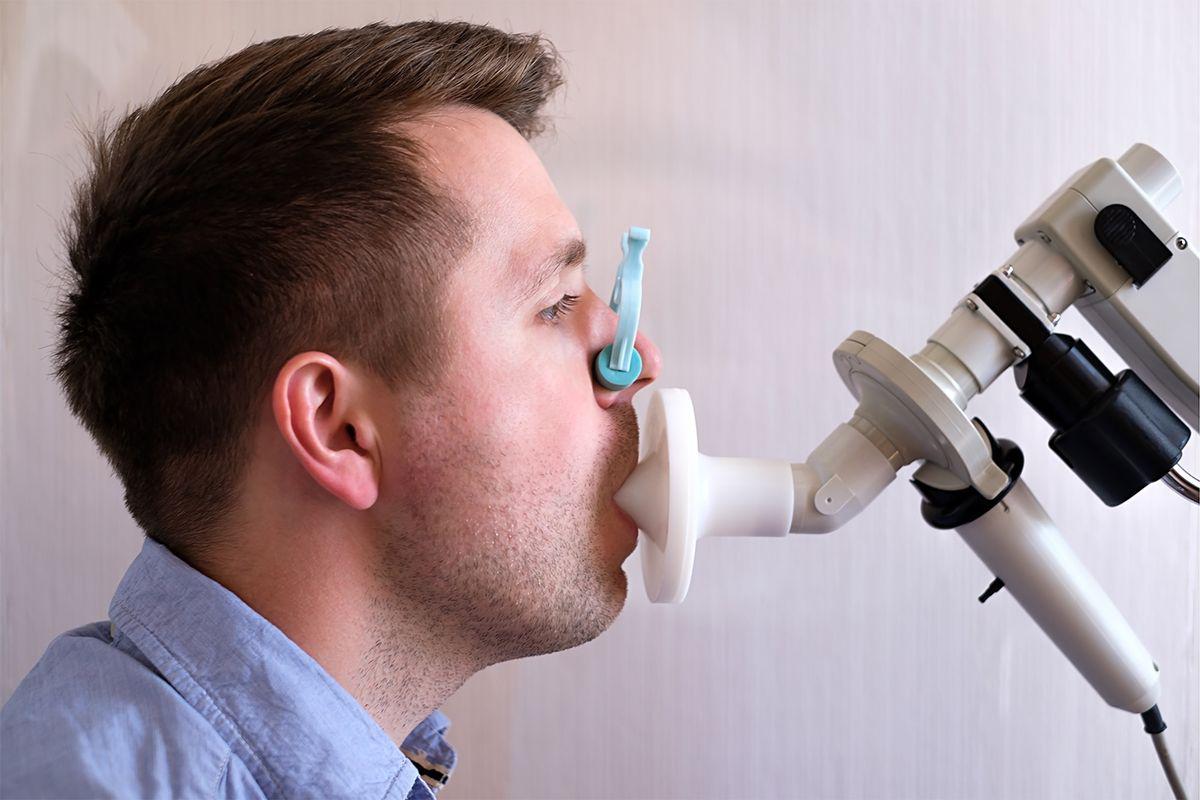

The Non-invasive Pulmonary Function Test our Best Health Care Professional performs to measure a patient's breathing and the functions of his/her lungs.